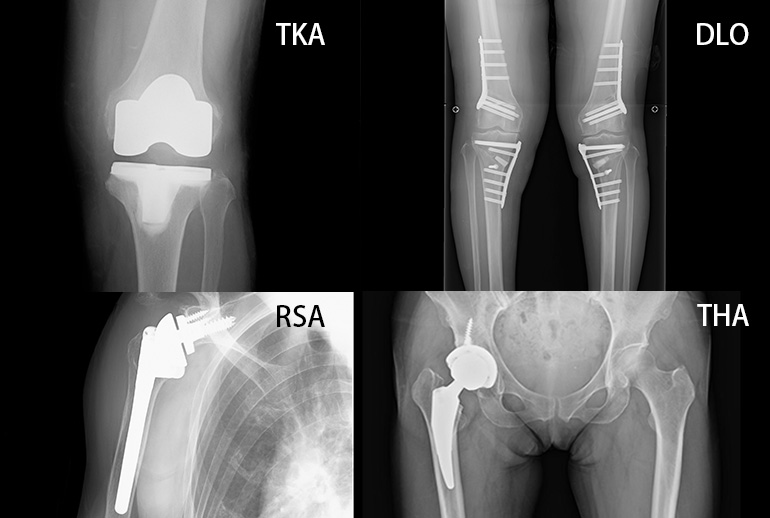

• ・変形性関節症に対しての人工関節置換術(膝・肩・股関節)

• ・膝周囲骨切り術(HTO、DFO、DLO)

膝靭帯損傷(前十字靭帯・内外側側副靭帯など)、半月板損傷、膝蓋骨脱臼、変形性関節症(膝)、前十字靱帯再建、半月板縫合、膝周囲骨切り術(HTO、DFO、DLO)、人工関節置換術(膝)

肩腱板断裂、反復性肩関節脱臼、変形性関節症(肩)、腱板縫合、肩脱臼に対するバンカート手術、リバース型人工関節置換術